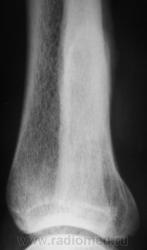

Пациент, в течение последних 2-х лет, жалуется на боли в нижней трети голени. Сегодня, хирургом, пациентка направлена на рентгенографию костей дистальной трети голени и голеностопного сустава. Что посоветуете уважаемые коллеги?

А что здесь советевать? Межберцовый неоартроз, вероятно, травматического генеза. Косой перелом н/л с признаками неполной консолидации. Попробуйте при производстве боковых снимков г/ст с-ва ( при травме) приподнимать пятку на 2-3 см.

Доброй ночи! Разволокнение коркового слоя, нечеткий очаг деструкции. Правда, нет секвестра. Если на увеличении не пригрезилось, то и линейный периостит. Вообще-то ответ был интуитивный, без логических обоснований. Ошиблась?